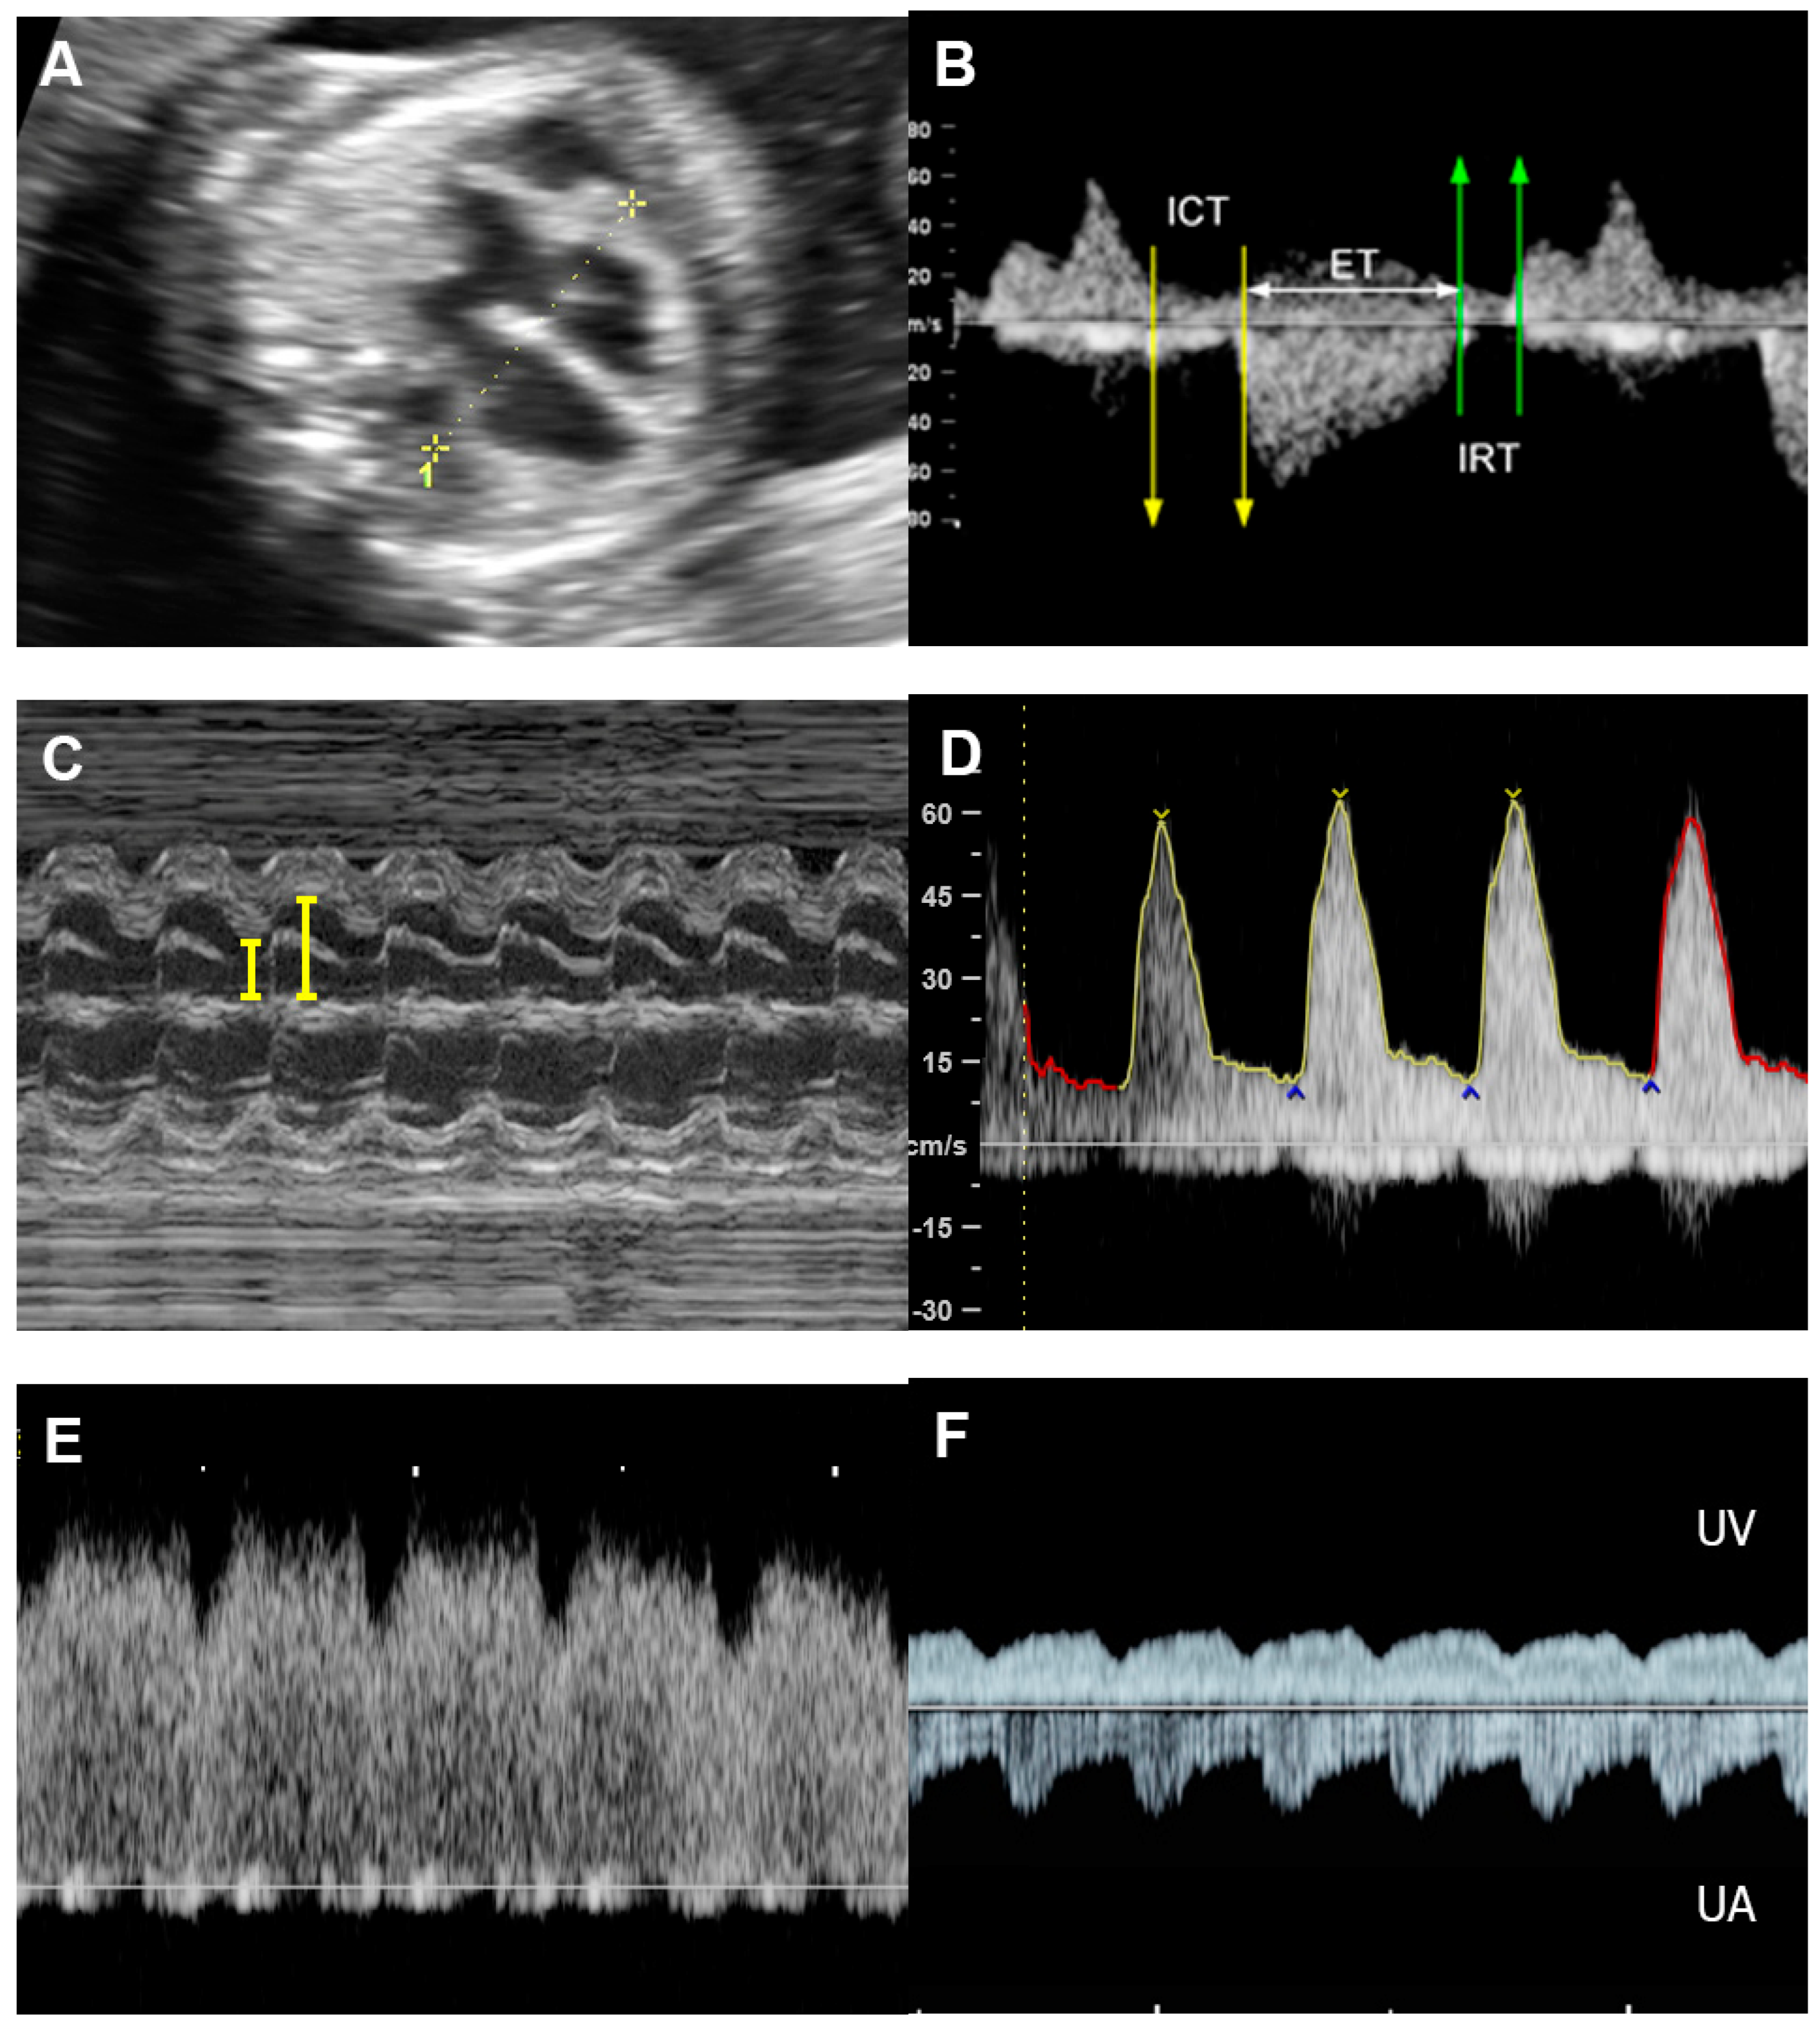

4.5. The Myocardial Performance Index (MPI)

- Soveral, I.; Crispi, F.; Guirado, L.; García-Otero, L.; Torres, X.; Bennasar, M.; Sepúlveda-Martínez, Á.; Nogué, L.; Gratacós, E.; Martínez, J.M.; et al. Fetal cardiac filling and ejection time fractions by pulsed-wave Doppler: Reference ranges and potential clinical application. Ultrasound Obstet. Gynecol. 2021, 58, 83–91. [Google Scholar] [CrossRef]

- Tongprasert, F.; Srisupundit, K.; Luewan, S.; Traisrisilp, K.; Jatavan, P.; Tongsong, T. Fetal isovolumetric time intervals as a marker of abnormal cardiac function in fetal anemia from homozygous alpha thalassemia-1 disease. Prenat. Diagn. 2017, 37, 1028–1032. [Google Scholar] [CrossRef]